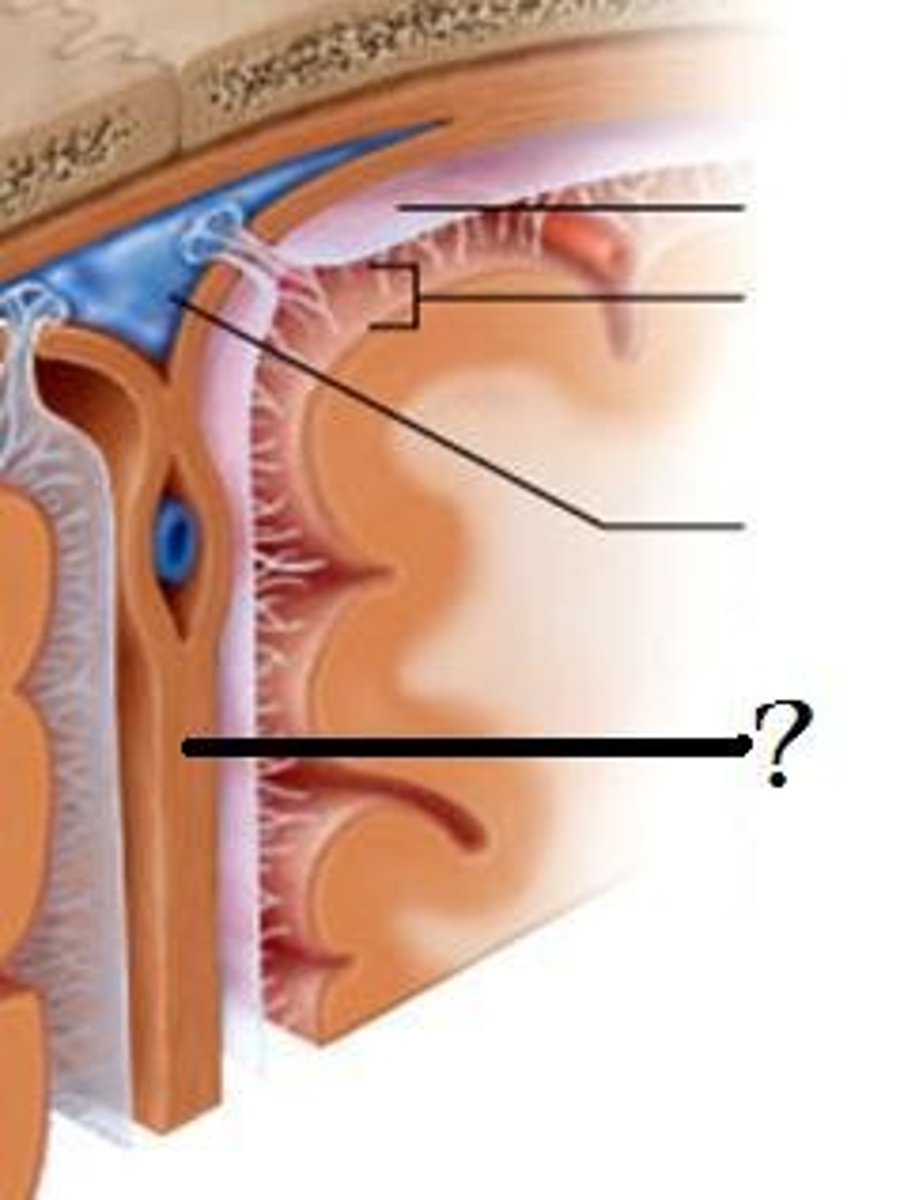

arachnoid mater

middle layer of meninges, weblike

what is in the subarachnoid space?

cerebrospinal fluid

pia mater

"delicate mother," innermost layer of meninges

what attaches the pia mater to the surface of the brain?

collagen fibers

choroid plexus

on the floor of all the ventricles, produces CSF

arachnoid villi

reabsorb/drain CSF into venous blood